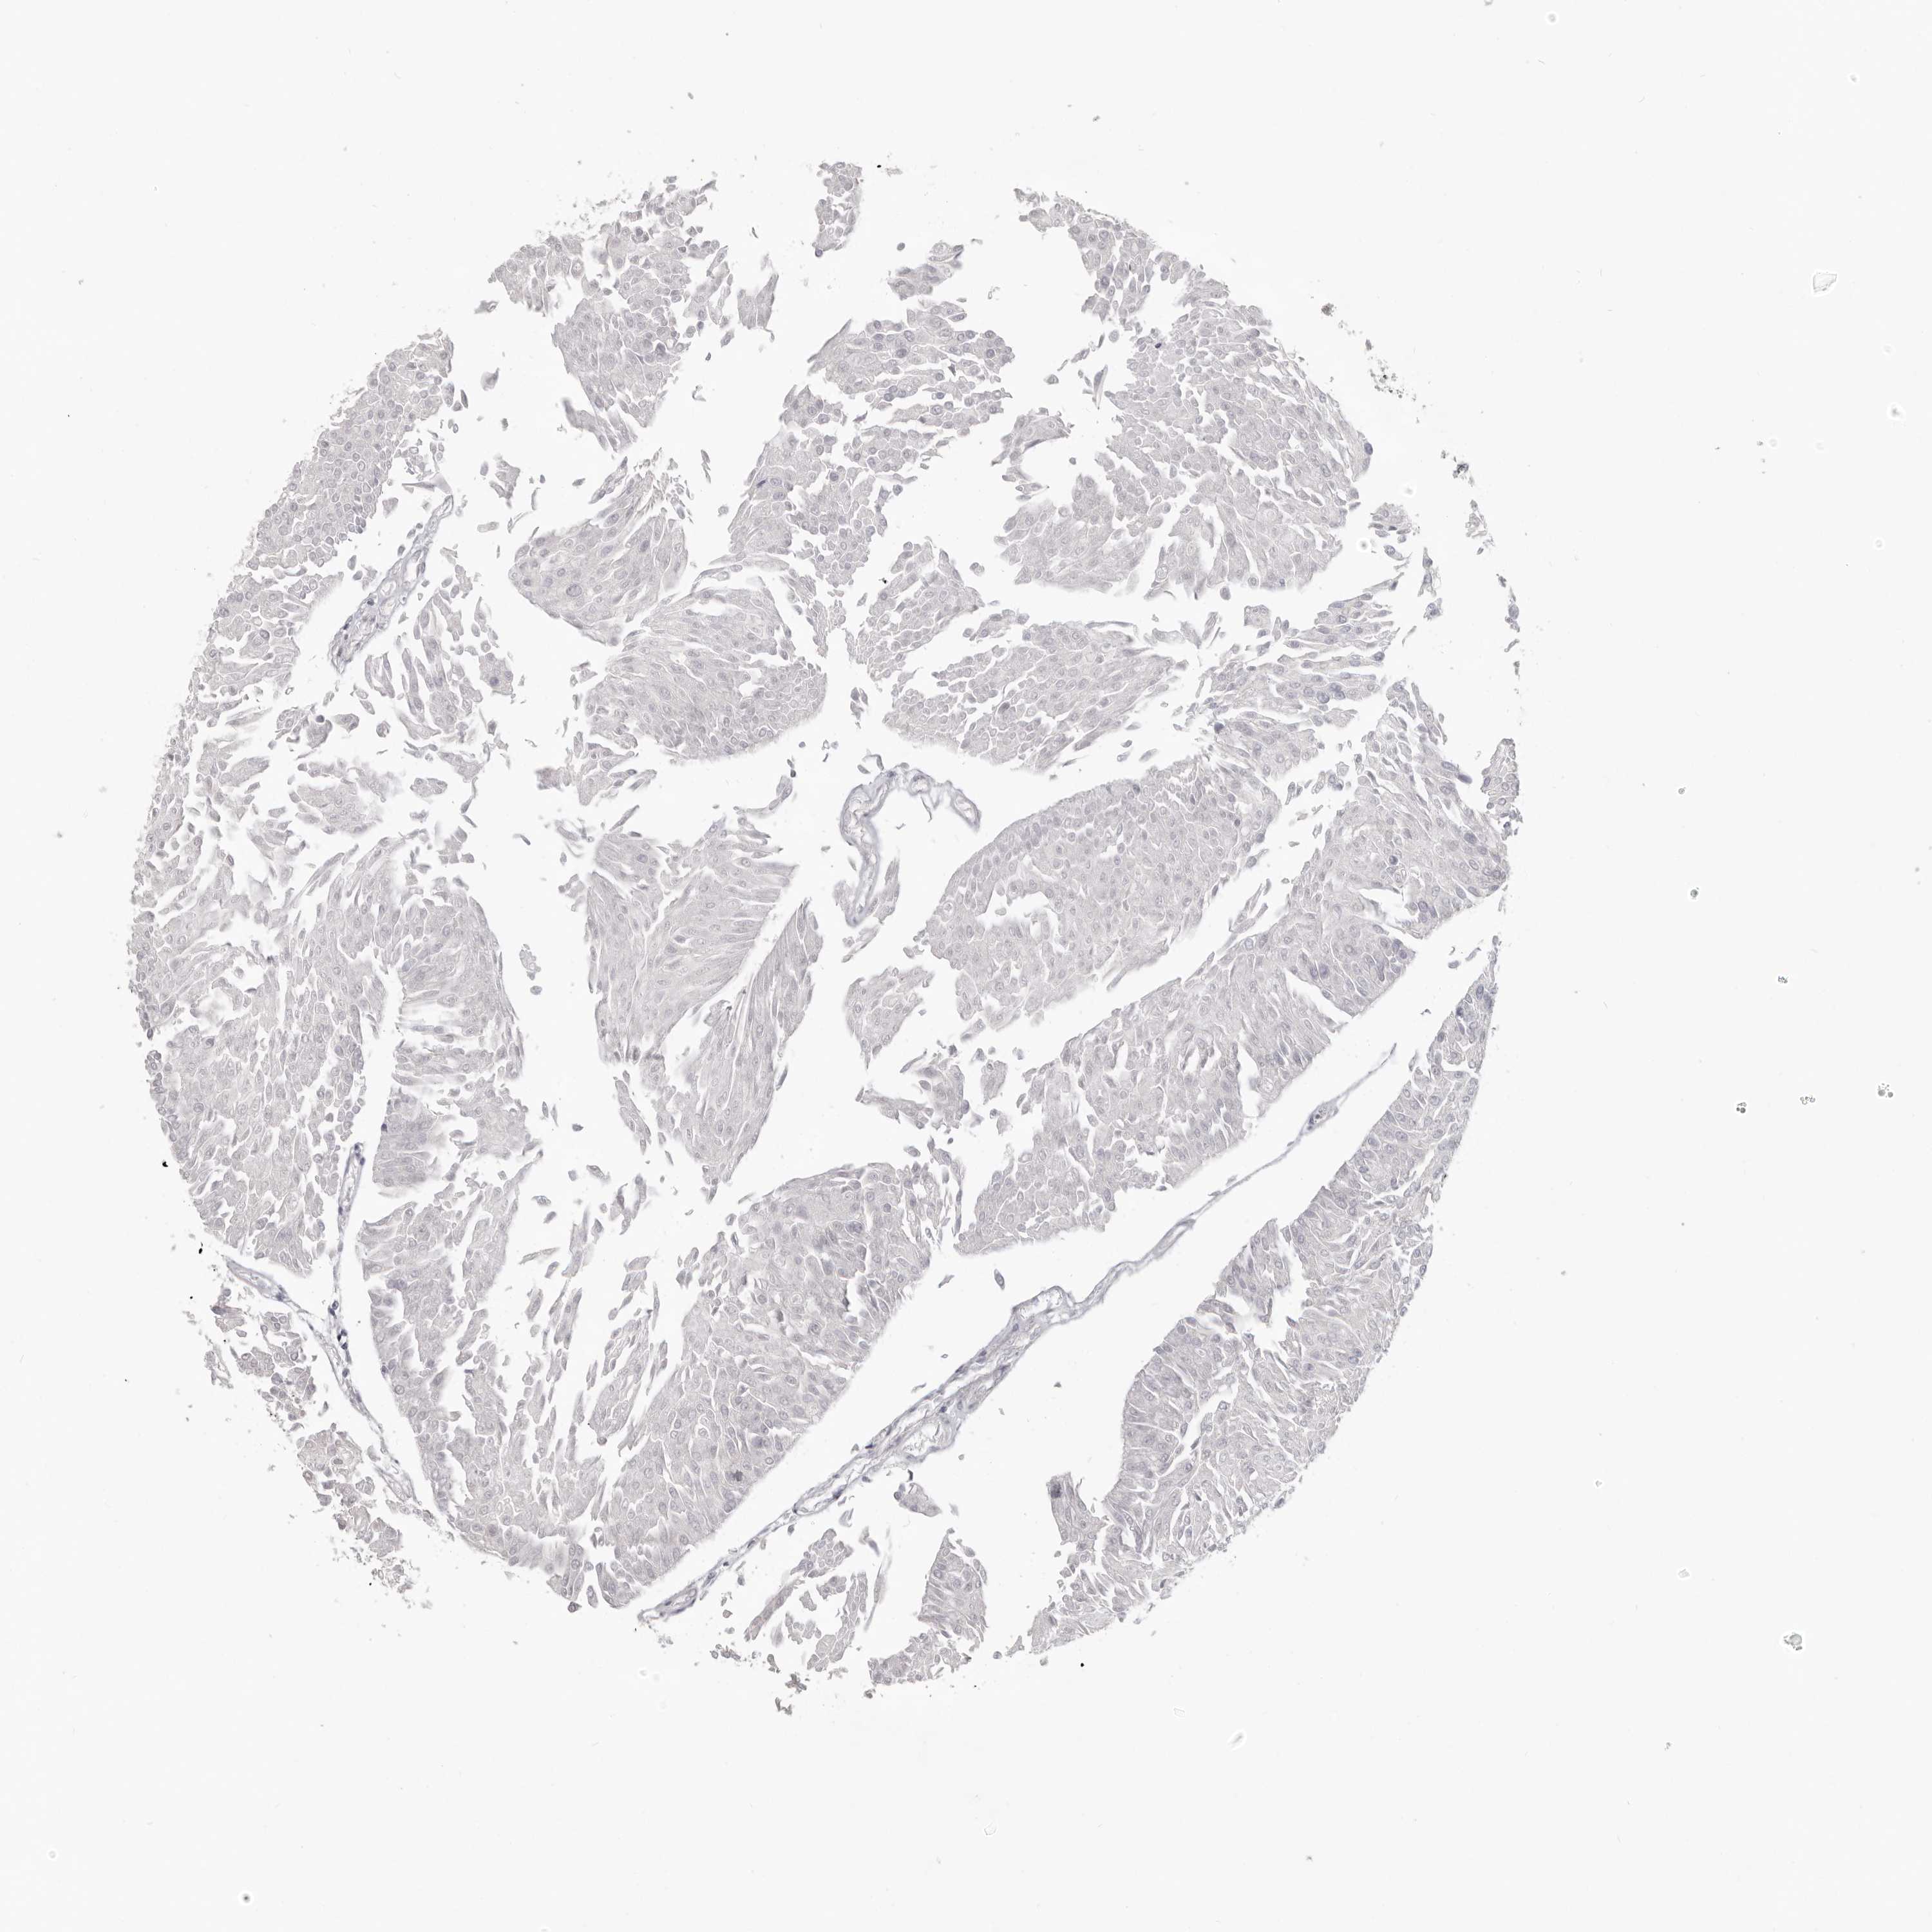

UROTHELIAL CANCER - Protein expressioni

A mouse-over function shows sample information and annotation data. Click on an image to view it in a full screen mode. Samples can be filtered based on level of antibody staining by selecting one or several of the following categories: high, medium, low and not detected. The assay and annotation is described here.

Note that samples used for immunohistochemistry by the Human Protein Atlas do not correspond to samples in the TCGA dataset.

Antibody stainingi

Antibody staining in the annotated cell types in the current human tissue is reported as not detected, low, medium, or high, based on conventional immunohistochemistry profiling in selected tissues. This score is based on the combination of the staining intensity and fraction of stained cells.

Each image is clickable and will lead to virtual microscopy that enables deeper exploration of all samples and also displays staining intensity scores, fraction scores and subcellular localization as well as patient and tissue information for each sample.

Antibody HPA029272

Staining

High

Medium

Low

Not detected

Intensity

Strong

Moderate

Weak

Negative

Quantity

>75%

75%-25%

<25%

None

Location

Urothelial carcinoma, Low grade

Urothelial carcinoma, High grade